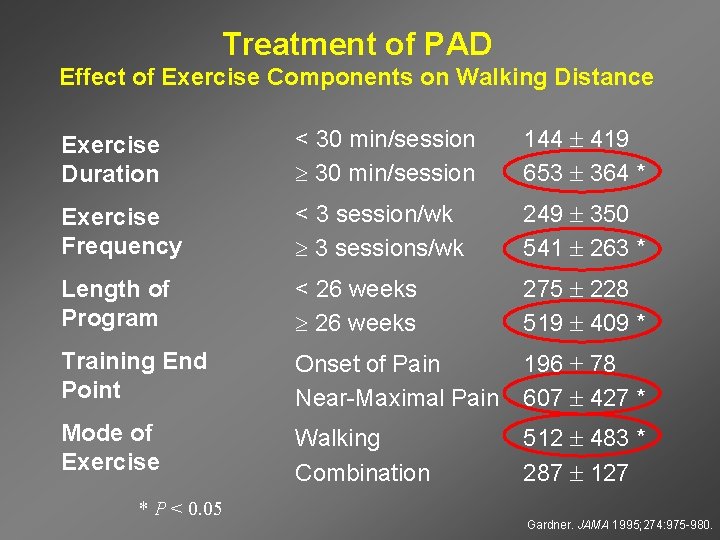

Treatment of PAD Effect of Exercise Components on Walking Distance Exercise Duration < 30 min/session 144 419 653 364 * Exercise Frequency < 3 session/wk 3 sessions/wk 249 350 541 263 * Length of Program < 26 weeks 275 228 519 409 * Training End Point Onset of Pain Near-Maximal Pain 196 78 607 427 * Mode of Exercise Walking Combination 512 483 * 287 127 * P < 0. 05 Gardner. JAMA 1995; 274: 975 -980.